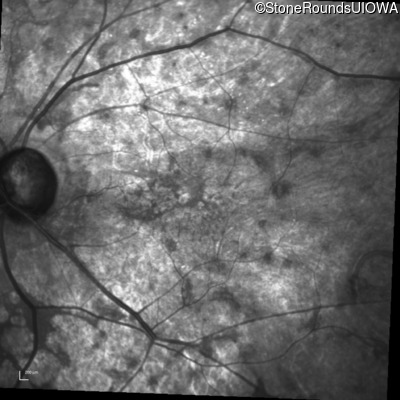

Infrared Fundus Photograph - Left - 20/80 -1

Exemplar